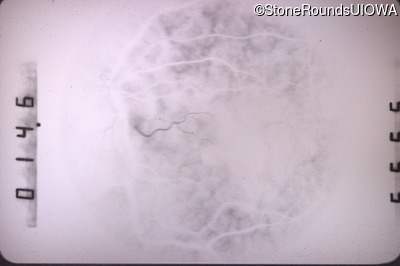

Fluorescein Angiography - Left - 20/160

Exemplar